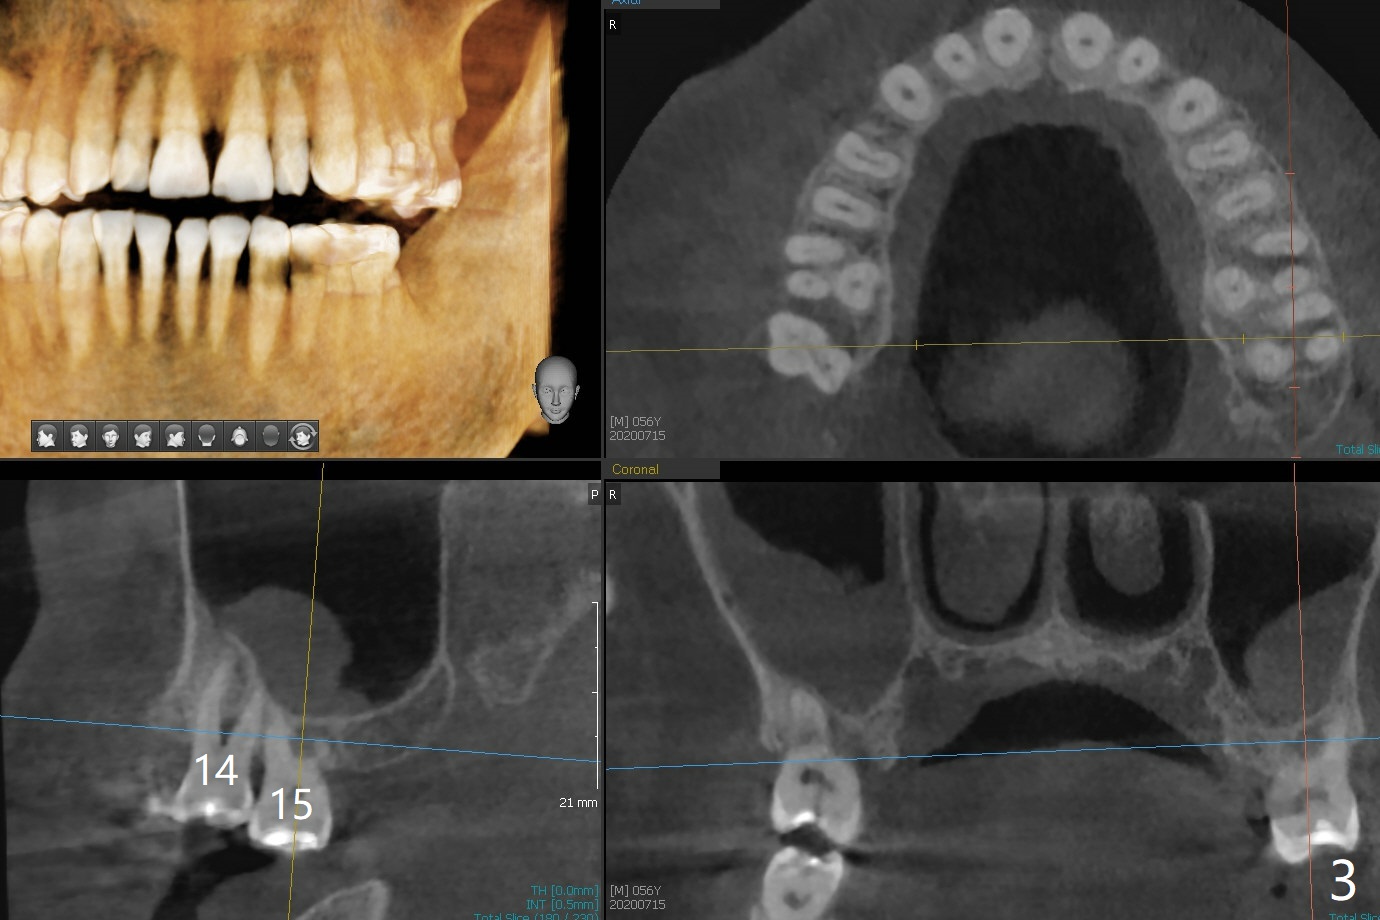

A 56-year-old man (smoker) has pain at #2 (Fig.1-3 thickened sinus membrane (R>L), C: mucous retention cyst) associated with subgingival crack (Fig.4 arrowheads). A 5x8.5 mm implant will be immediately placed with sinus lift aided by PRF membrane (Fig.5). A narrow implant will be placed at #30 (Fig.6).